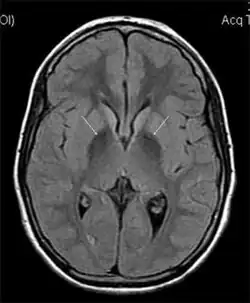

MRI hypointensity (white arrows) in the globus pallidi that indicates the presence of iron deficiencies which would be seen in a diagnosis of Aceruloplasminemia | |

Diagnosis of this disorder depends on blood tests demonstrating the absence of serum ceruloplasmin, combined with low serum copper concentration, low serum iron concentration, high serum ferritin concentration, or increased hepatic iron concentration. MRI scans can also confirm a diagnosis; abnormal low intensities can indicate iron accumulation in the brain.[5]